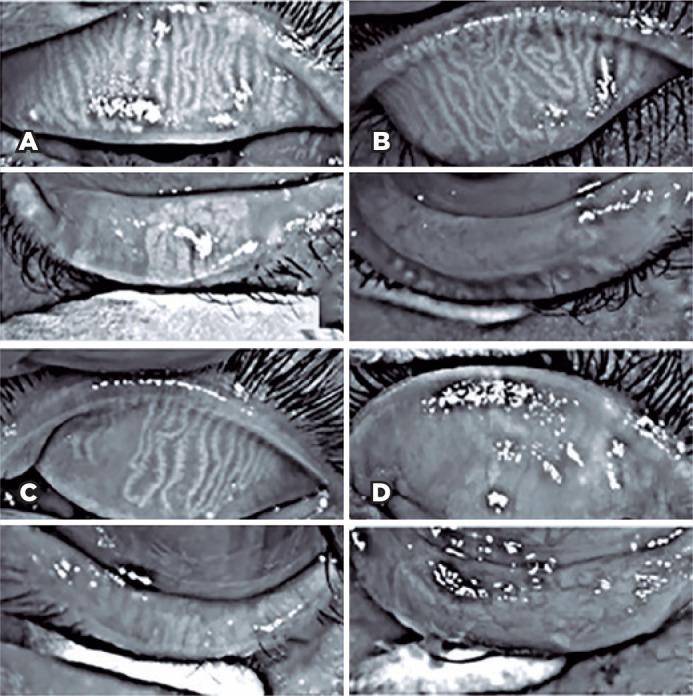

This cross-sectional study evaluated patients with xeroderma pigmentosum. All patients underwent a comprehensive and standardized interview. The best-corrected visual acuity of each eye was determined. Detailed ophthalmic examination was conducted, including biomicroscopy examination of the ocular surface, Schirmer test type I, and meibography, and fundus examination was also performed when possible. Meibomian gland dysfunction was assessed by non-contact meibography using Oculus Keratograph® 5M (OCULUS Inc., Arlington, WA, USA). Saliva samples were collected using the Oragene DNA Self-collection kit (DNA Genotek Inc., Ottawa, Canada), and DNA was extracted as recommended by the manufacturer. Factors associated with abnormal meiboscores were assessed using generalized estimating equation models.

A total of 42 participants were enrolled, and 27 patients underwent meibography. The meiboscore was abnormal in the upper eyelid in 8 (29.6%) patients and in the lower eyelid in 17 (62.9%). The likelihood of having abnormal meiboscores in the lower eyelid was 16.3 times greater than that in the upper eyelid. In the final multivariate model, age (p=0.001), mutation profile (p=0.006), and presence of ocular surface malignant tumor (OSMT) (p=0.014) remained significant for abnormal meiboscores. For a 1-year increase in age, the likelihood of abnormal meiboscores increased by 12%. Eyes with OSMT were 58.8 times more likely to have abnormal meiboscores than eyes without ocular surface malignant tumor.

In the final model, age, xeroderma pigmentosum profile, previous cancer, and clinical alterations on the eyelid correlated with a meiboscore of ≥2. Meibomian gland dysfunction was common in patients with xeroderma pigmentosum, mainly in the lower eyelid. The severity of Meibomian gland dysfunction increases with age and is associated with severe eyelid changes.